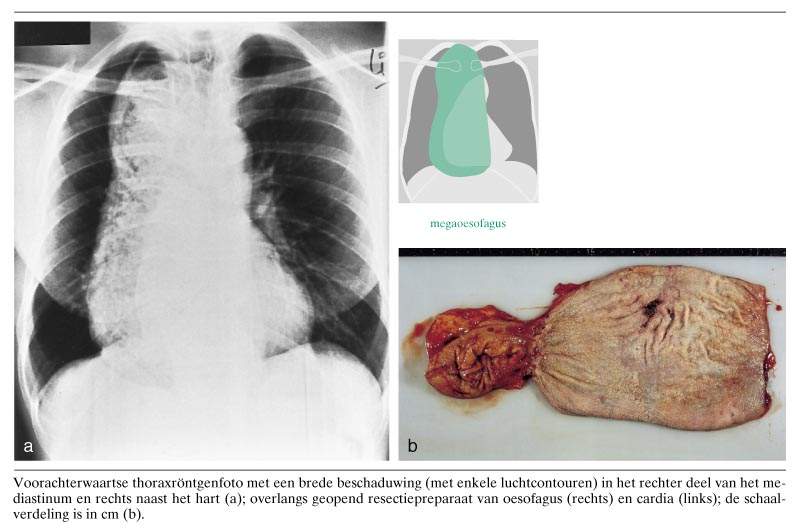

Een 49-jarige man van Nigeriaanse afkomst had als kind al last van langzaam progressieve dysfagie, in het bijzonder regurgitatie en hoesten bij plat liggen. Na immigratie in Nederland stelde hij zich op 28-jarige leeftijd onder medische behandeling. Op een thoraxfoto werd rechts paramediastinaal een beschaduwing waargenomen die bleek te berusten op een megaoesofagus als gevolg van een miskende achalasie. In eerste instantie werden herhaalde endoscopische pneumodilataties toegepast, met wisselend succes. Omdat de conservatieve therapie faalde - patiënt had inmiddels 4 kg gewicht verloren - en de oesofagus verder in omvang toenam (figuur), werd uiteindelijk besloten een oesofagusresectie…